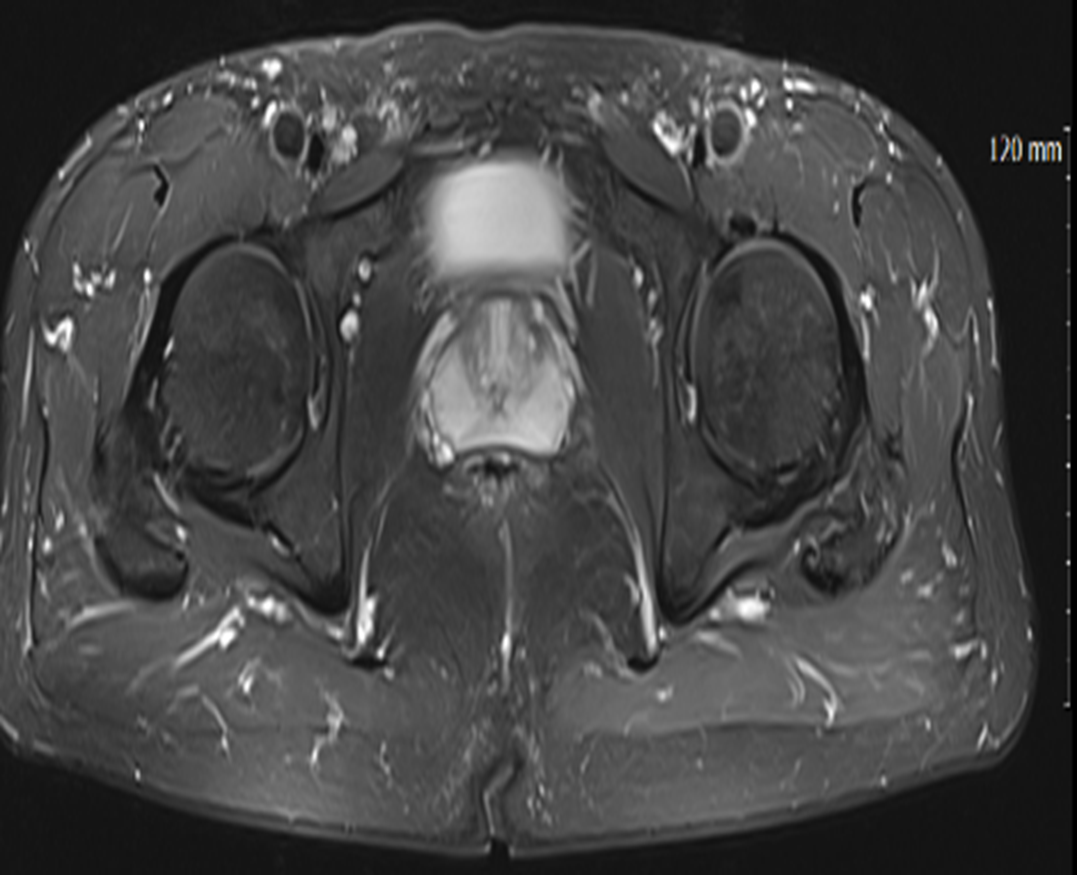

MRI 촬영을 통해 연부조직의 상태까지 자세히 살펴본 거죠.

그림3.png

<Fig 1. 고관절 유착성 관절낭염으로 진단된 MRI>

결과는 예상했던 대로였어요.

특발성 고관절 유착성 관절낭염

쉽게 말하면 관절 주변의 관절낭이라는 주머니가 염증과 함께 유착되면서

관절의 움직임이 제한되고 통증이 생기는 질환이에요.